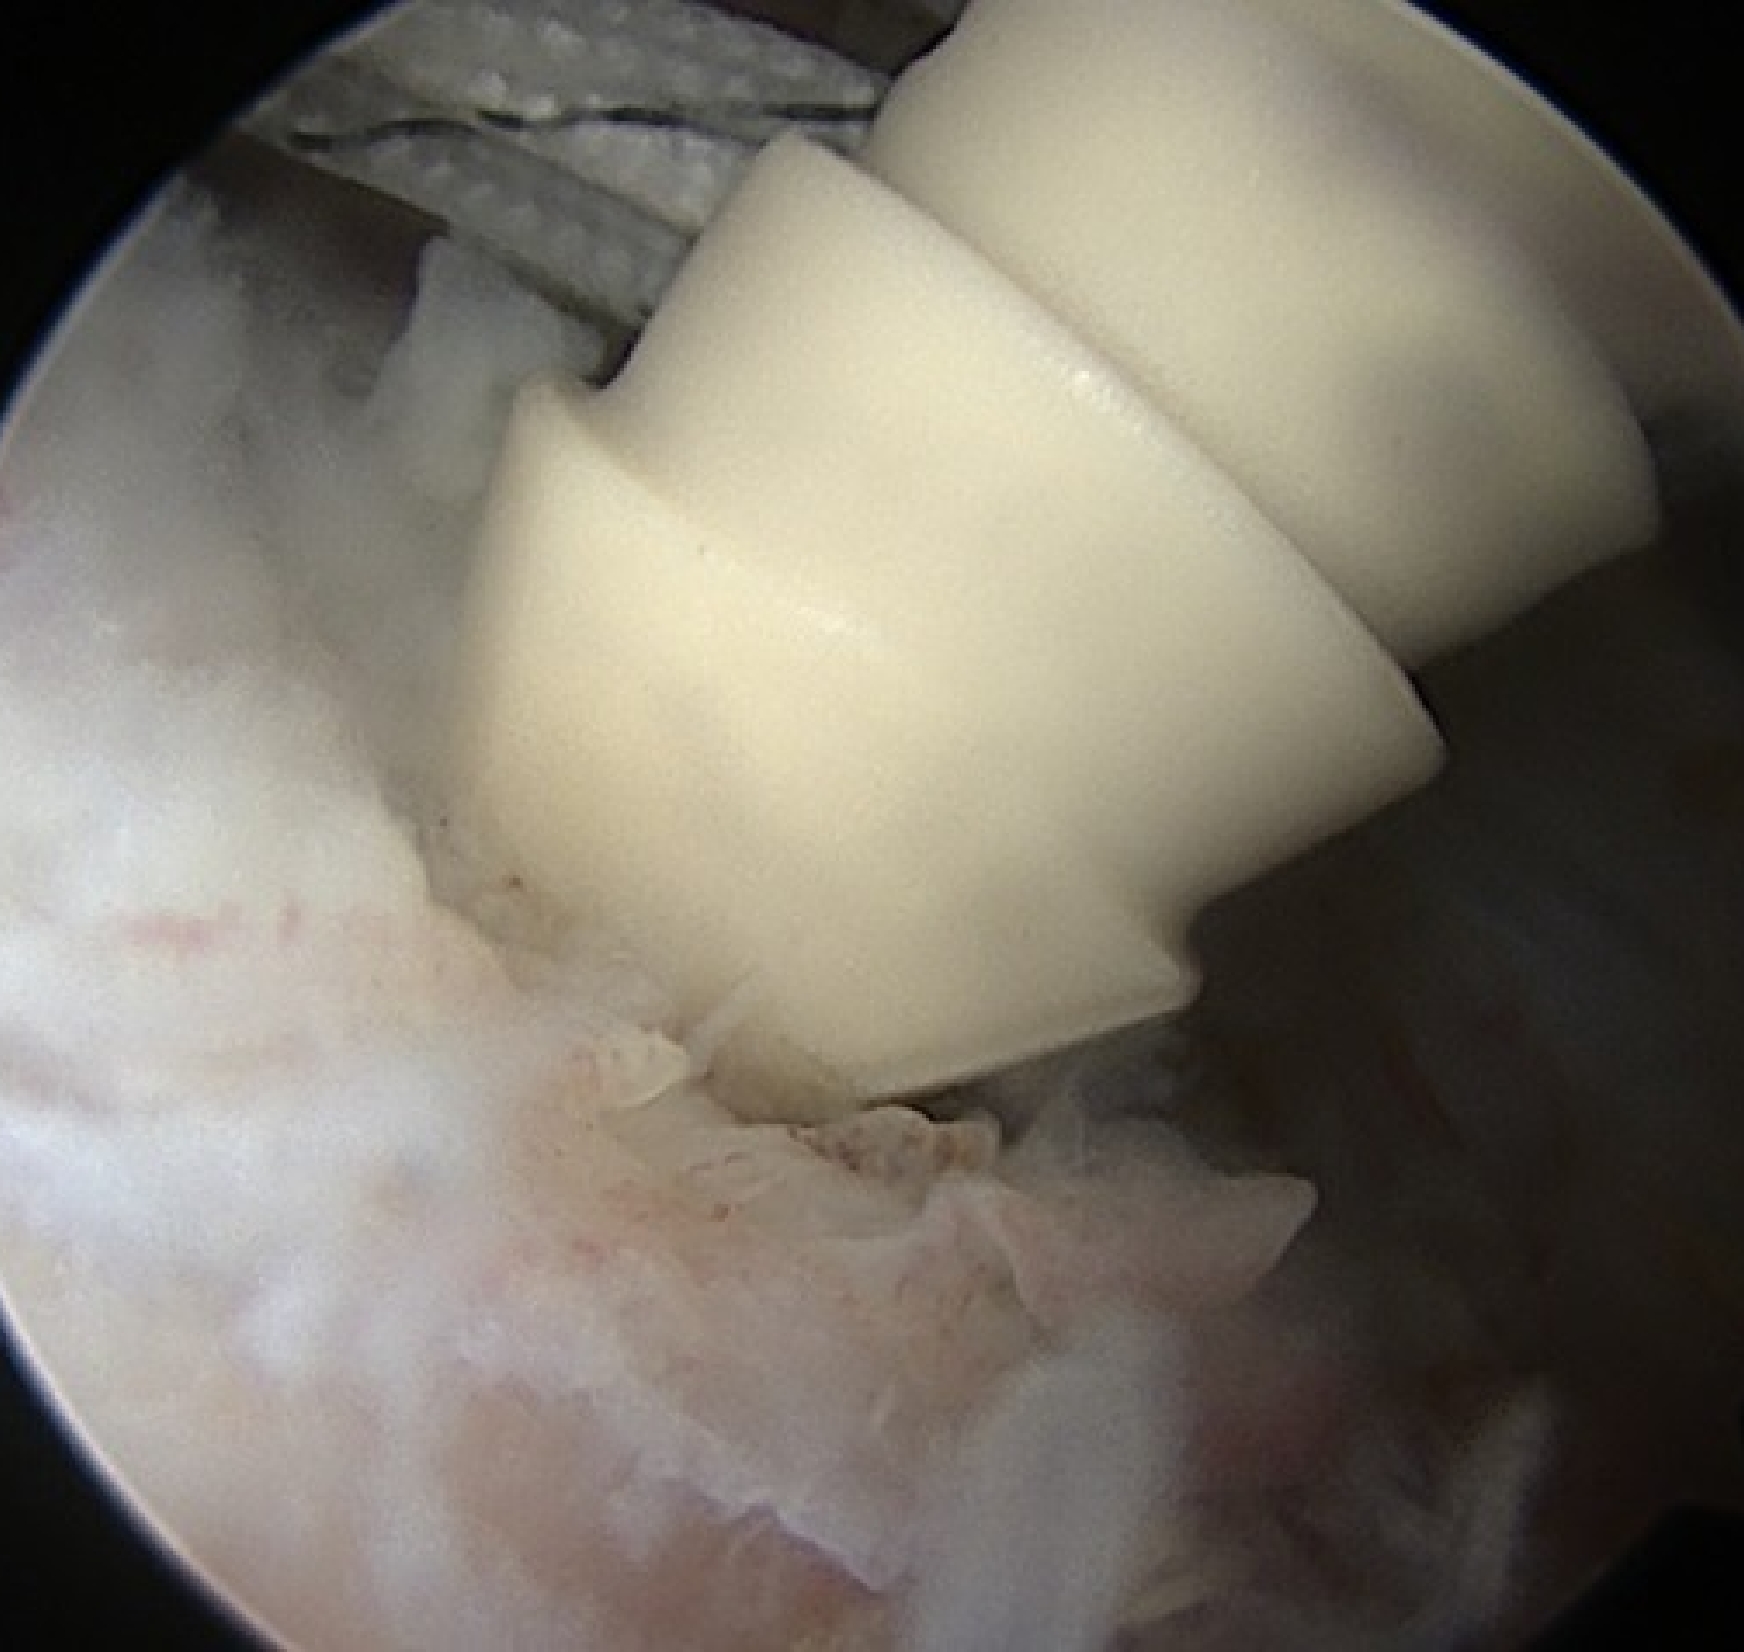

Suture-bridge完成

露出していた骨頭は見えなくなり、腱板で覆われています。